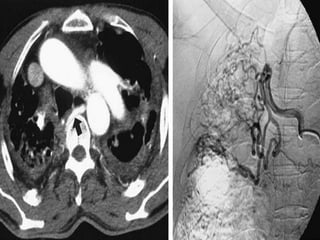

Bronchial artery embolization